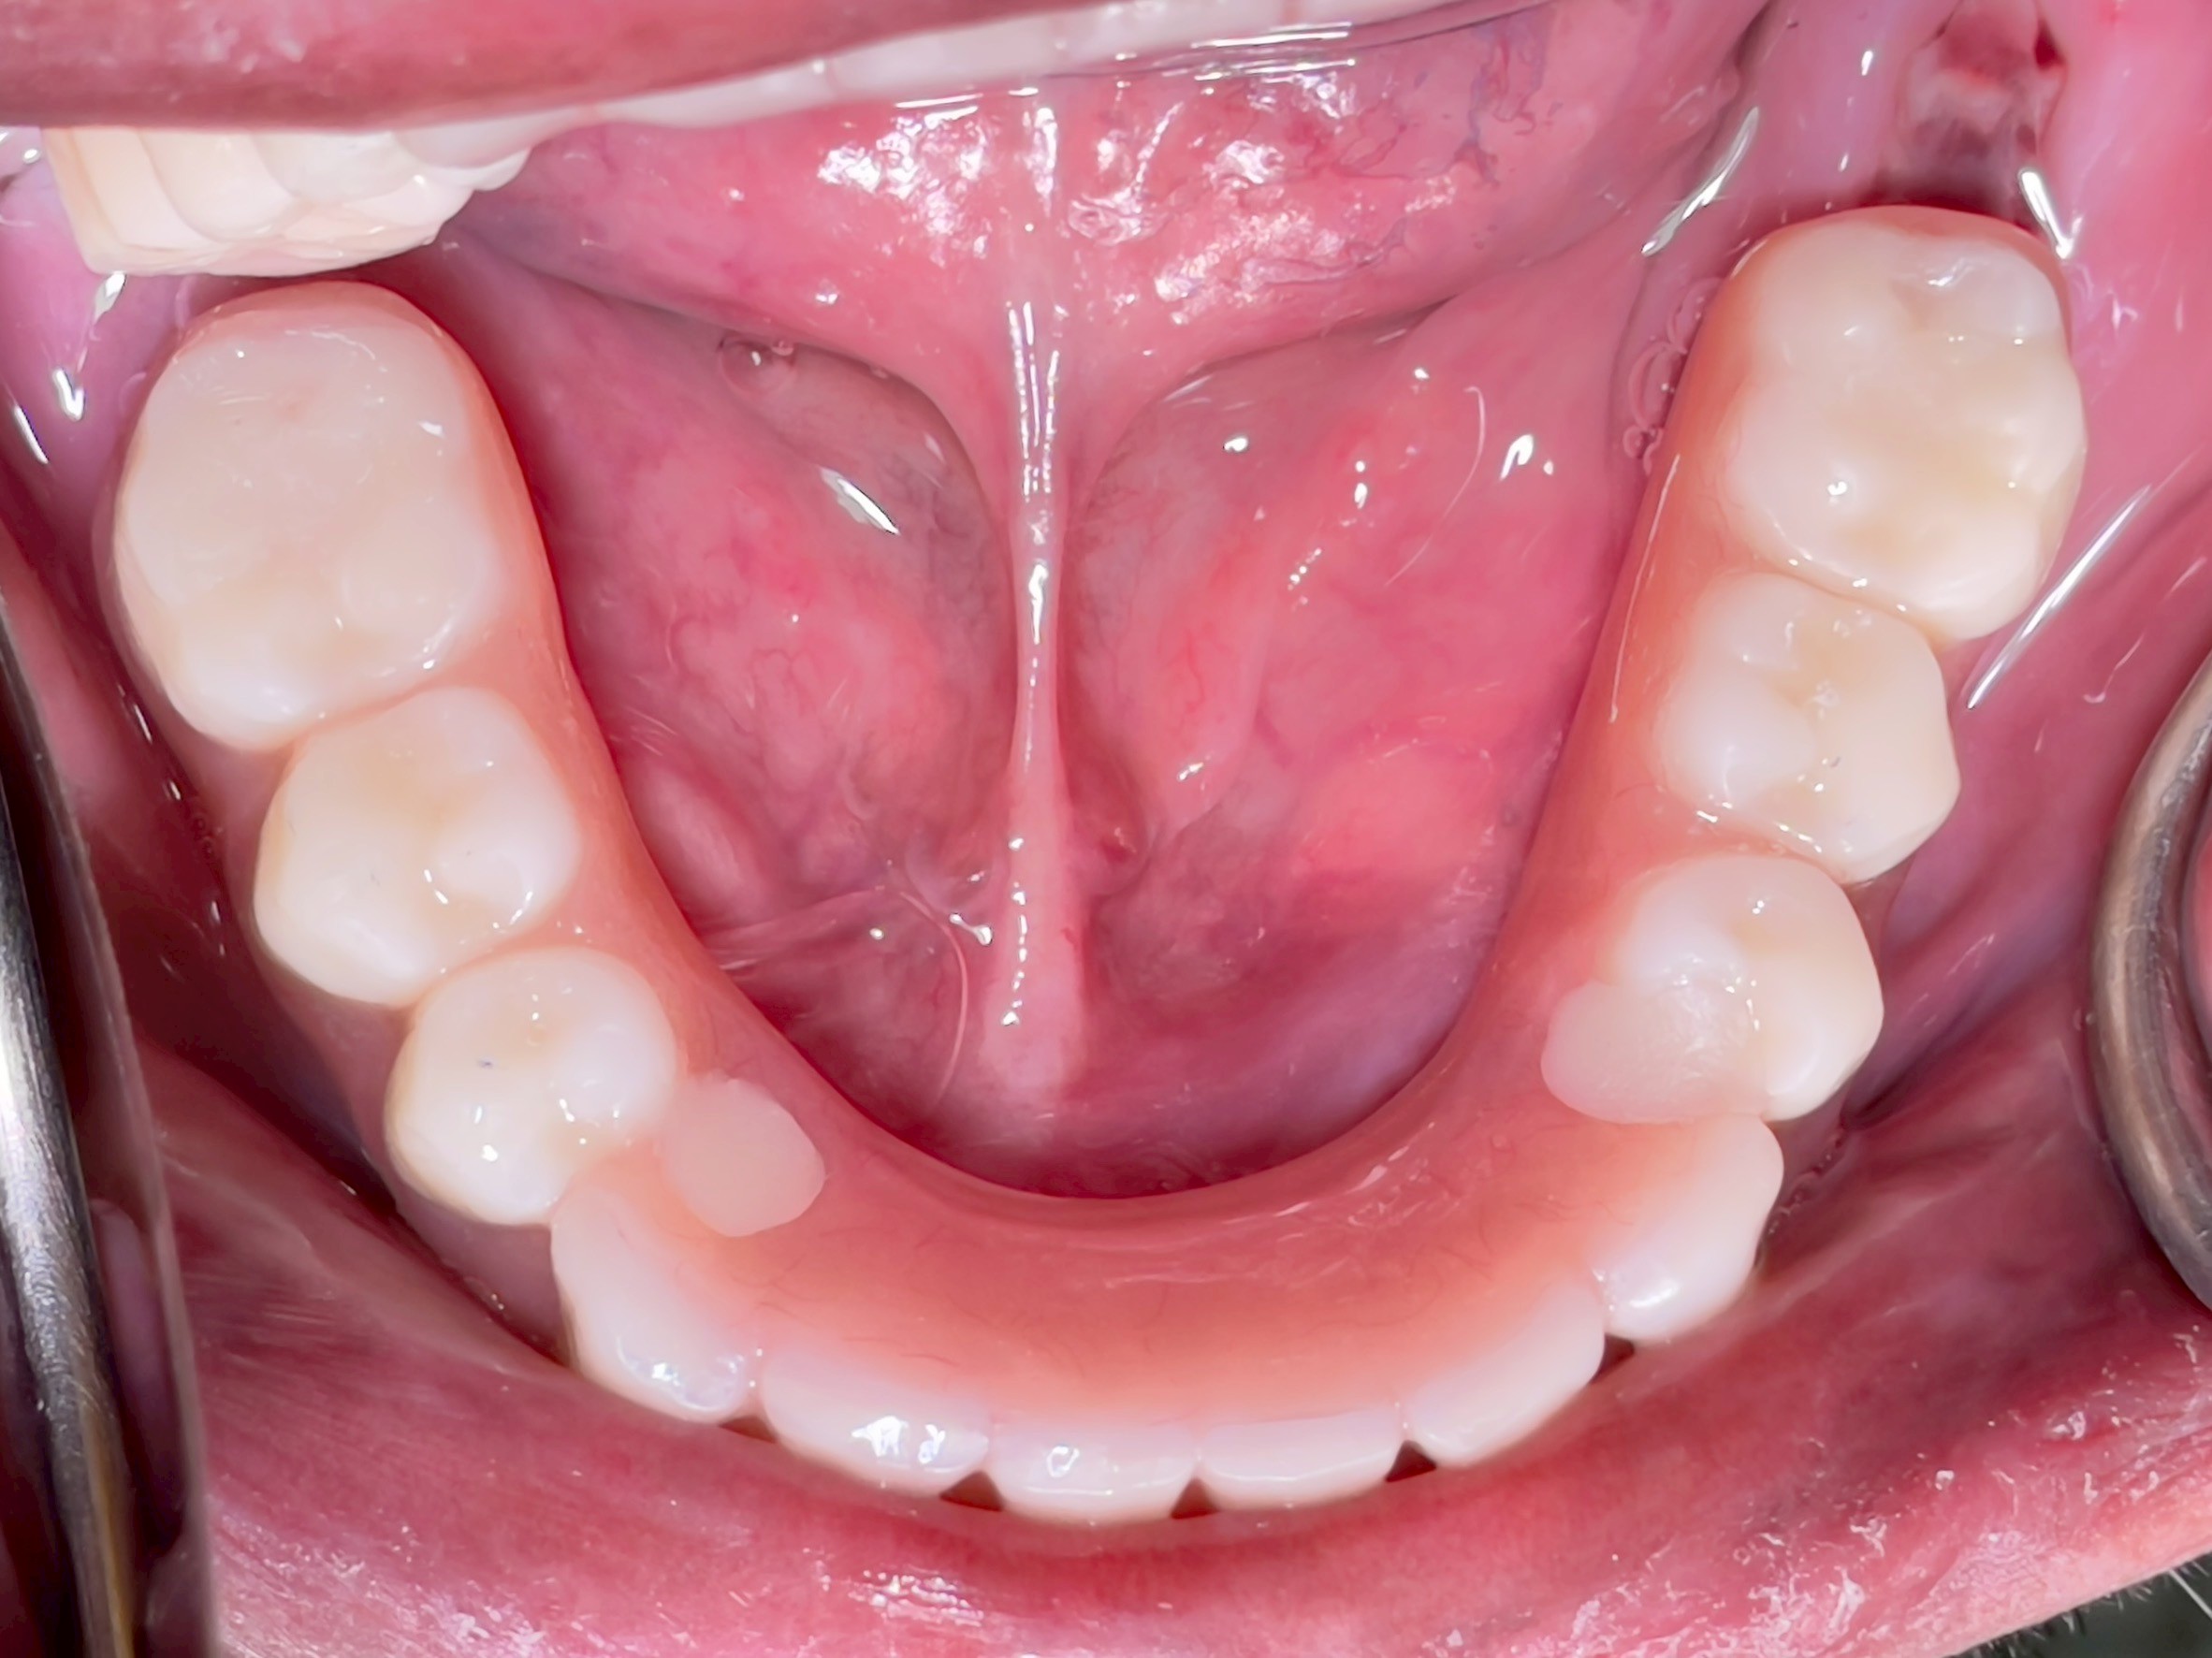

All-on-4 Implants Lower Jaw + Partial Denture Upper Jaw